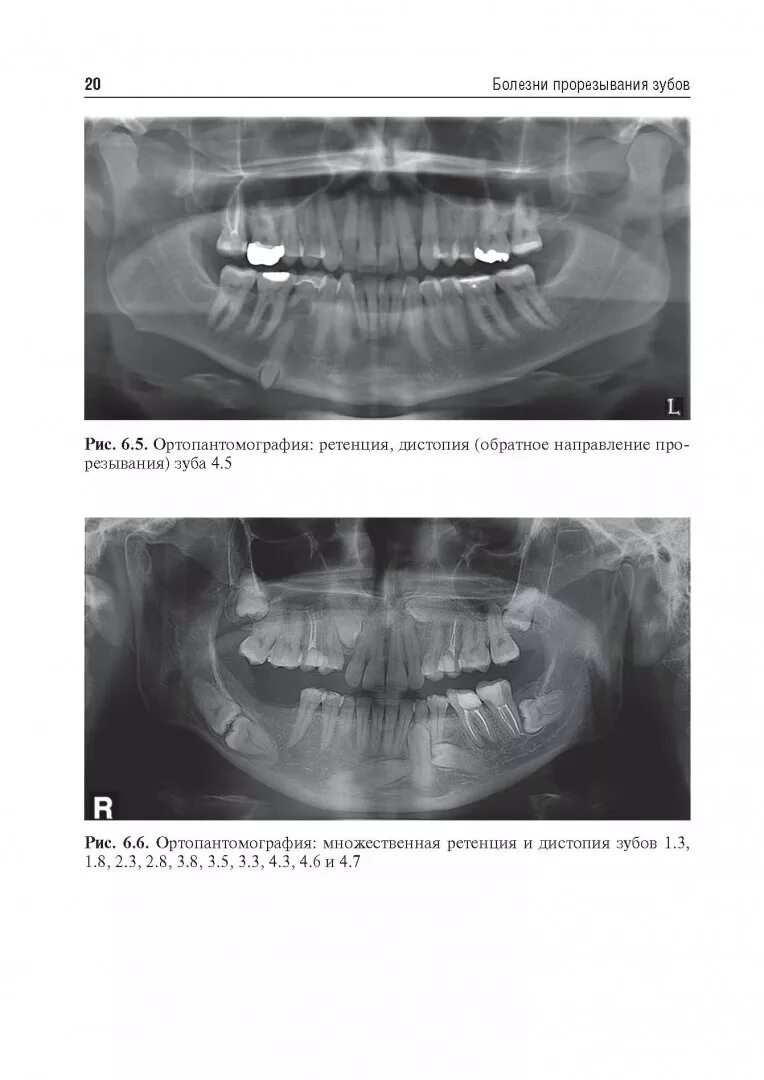

Дистопированный зуб мкб 10